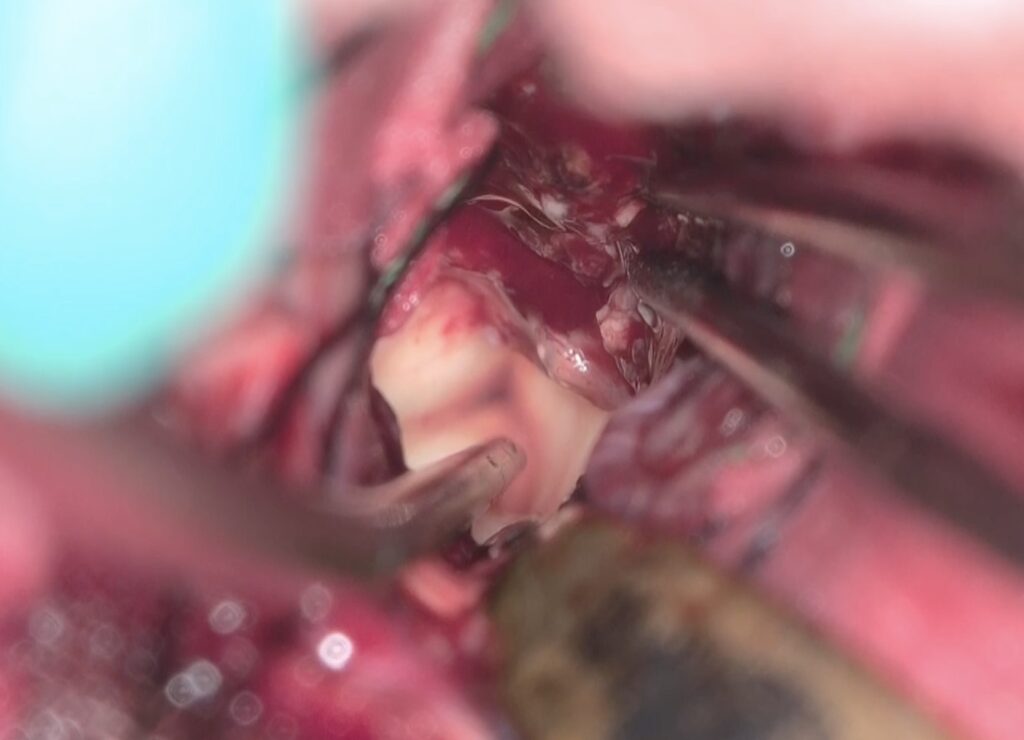

Trans-lamina terminalis approach、何度もやった古典的なアプローチです。A2と伴奏し縦走する視床下部動脈を温存して、その間隙から腫瘍を減圧していきます。

腫瘍を減圧し、最後に起こして、中脳水道や脳底動脈を確認しました。視交差の下は減圧にとどめました。